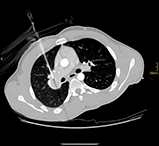

Nach Innsbruck kam Glodny aufgrund eines persönlichen Treffens mit o. Univ.-Prof. Dr. Werner Jaschke, dem Leiter der Innsbrucker Universitätsklinik für Radiologie. „Aus einem zunächst nur kurz angesetztem Termin bei ihm wurde ein mehrstündiges Gespräch, in dem ich erfahren habe, was hier in Innsbruck alles möglich ist und wie ich hier arbeiten kann“, erzählt Glodny rückblickend. Insbesondere die interventionelle Radiologie, durch die vielfältige therapeutische Eingriffe etwa in der Behandlung der arteriellen Verschlusskrankheit, oder von Blutungen oder Aneurysmen, von Tumoren- oder Metastasen möglich geworden sind, fasziniert den Radiologen und Forscher. „Mit durch Hochfrequenzstrom erzeugter Hitze, z. B. dem Verfahren der sogenannten Radiofrequenzablation, können Tumore oder Metastasen in Organen wie Leber, Niere oder Lunge behandelt werden. Die Vorteile dabei sind, dass ein oder mehrere Tumore extrem zielgenau und gründlich zerstört werden können, die ganze Prozedur aber für die Patient:innen sehr schonend ist. Die Absprache mit den behandelnden Kolleg:innen zur Erstellung eines individuellen interdisziplinären Behandlungskonzeptes für jede einzelne Patientin und jeden einzelnen Patienten garantiert die beste Versorgung.“ Am Standort Innsbruck schätzt Glodny vor allem das hohe fachliche Know How und gerät dabei nahezu ins Schwärmen: „Hier wird interventionelle Radiologie in absoluter Perfektion betrieben! Vor allem von Professor Reto Bale, der ein absoluter Experte auch in der Behandlung großer Tumore ist, kann ich sehr, sehr viel lernen. Darüber hinaus ist auch die Zusammenarbeit mit den Kolleg:innen aus der Universitätsklinik für Neuroradiologie unheimlich wertvoll und effektiv.“